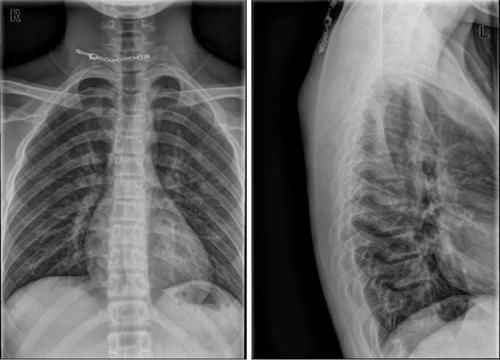

Case13:F,4y;腰痛1月余,加重半月。

文章插图

Case14:M,6y;双侧髋部疼痛1月余,加重伴不能行走半月。